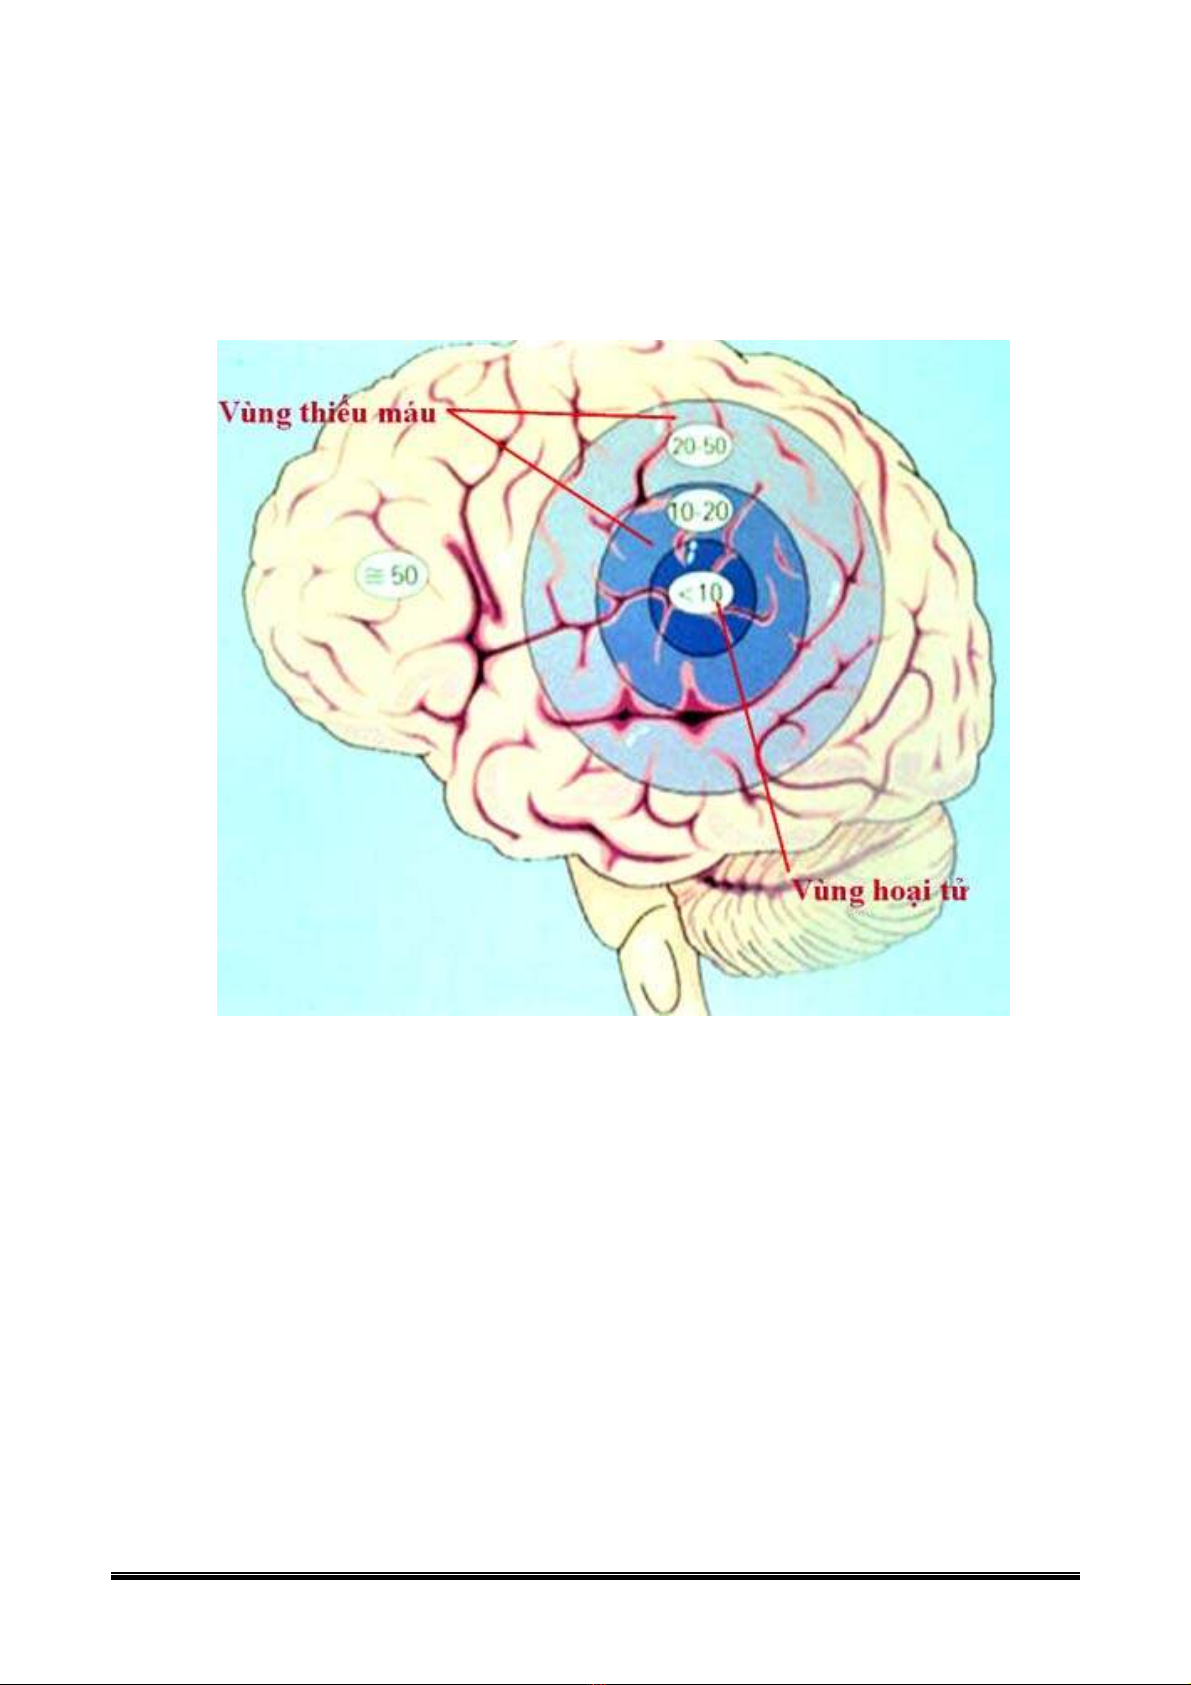

• Lưu lượng máu < 9 ml/100grams não/phút

→ Hoại tử = phù não = giảm đậm độ

• Các vùng chung quanh vùng hoại tử là vùng thiếu máu nhưng còn có khả năng hồi

phục. Tû träng c¸c vïng nµy nh− sau: